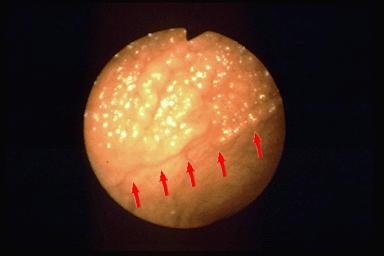

Nodule- aggregating adenoma with intra mucosal carcinoma showing diffuse tiny granular change.

Tokyo Pref., Cooperative study between National Cancer Center and Kyushu Cancer Center

Large intestine(Colon)/Rectum

Endoscopy

40 -

mucosa